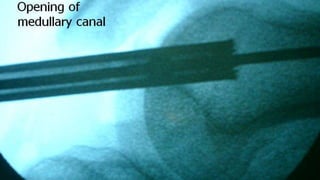

Distal Femur retrograde nailing

Brief steps of distal femoral retrograde nailing of femur